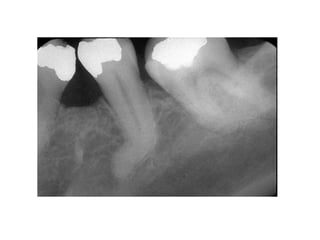

10. Dilaceration

Dilaceration adalah gangguan pada

pembentukan gigi yang menghasilkan bend or

curve dari gigi, baik pada akar maupun pada

mahkota.